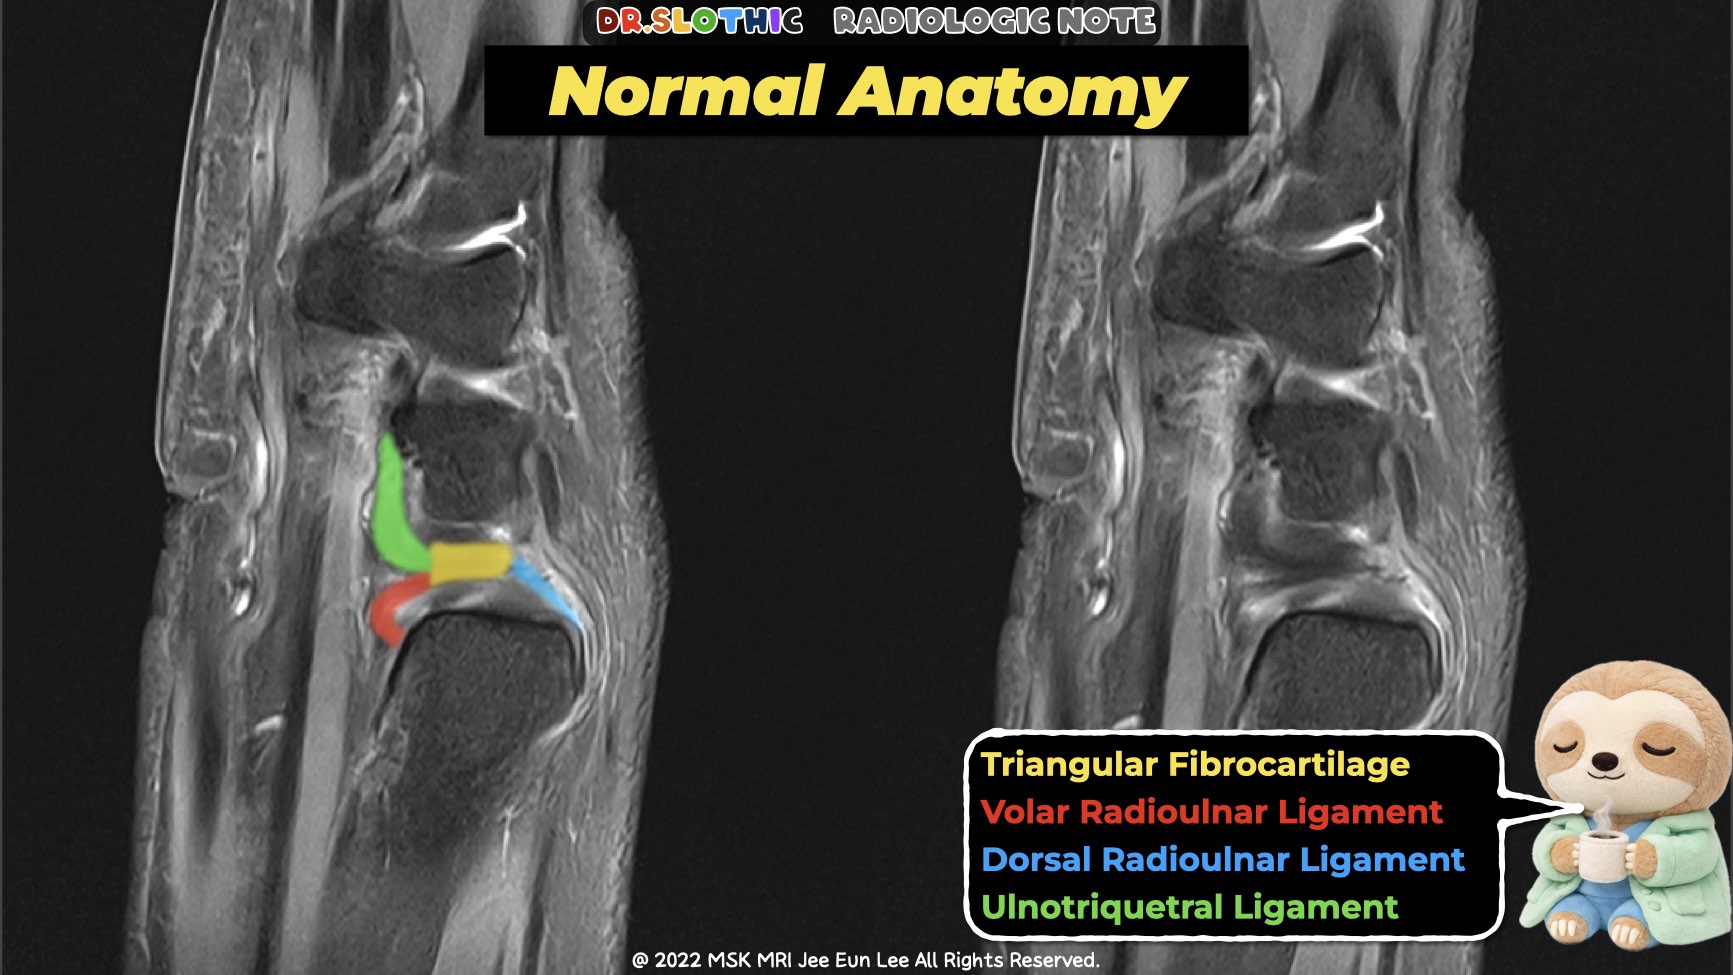

On sagittal wrist magnetic resonance imaging,

the triangular fibrocartilage complex should not be read as a single disc.

It represents a continuous ulnar-sided stabilizing system connecting the distal radioulnar joint to the ulnocarpal joint.

MRI Take-Home Message

On sagittal wrist magnetic resonance imaging:

disc → radioulnar ligaments → ulnocarpal ligaments

should be followed as one continuous stabilizing chain.

Instability rarely comes from the disc alone.